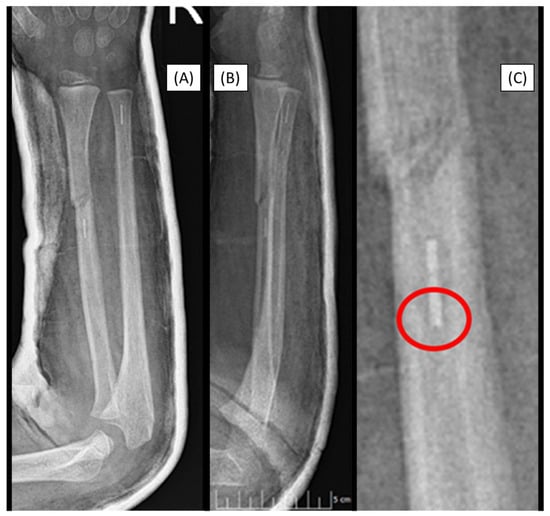

3.3. Case 3: Apical Implant Splitting